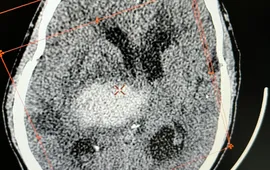

Cảnh báo xuất huyết não do tự ý bỏ thuốc huyết áp

VTV.vn - Thời gian gần đây, tình trạng người bệnh bị xuất huyết não nhập viện tăng cao tại Trung tâm Y tế huyện Thanh Thủy (Phú Thọ).